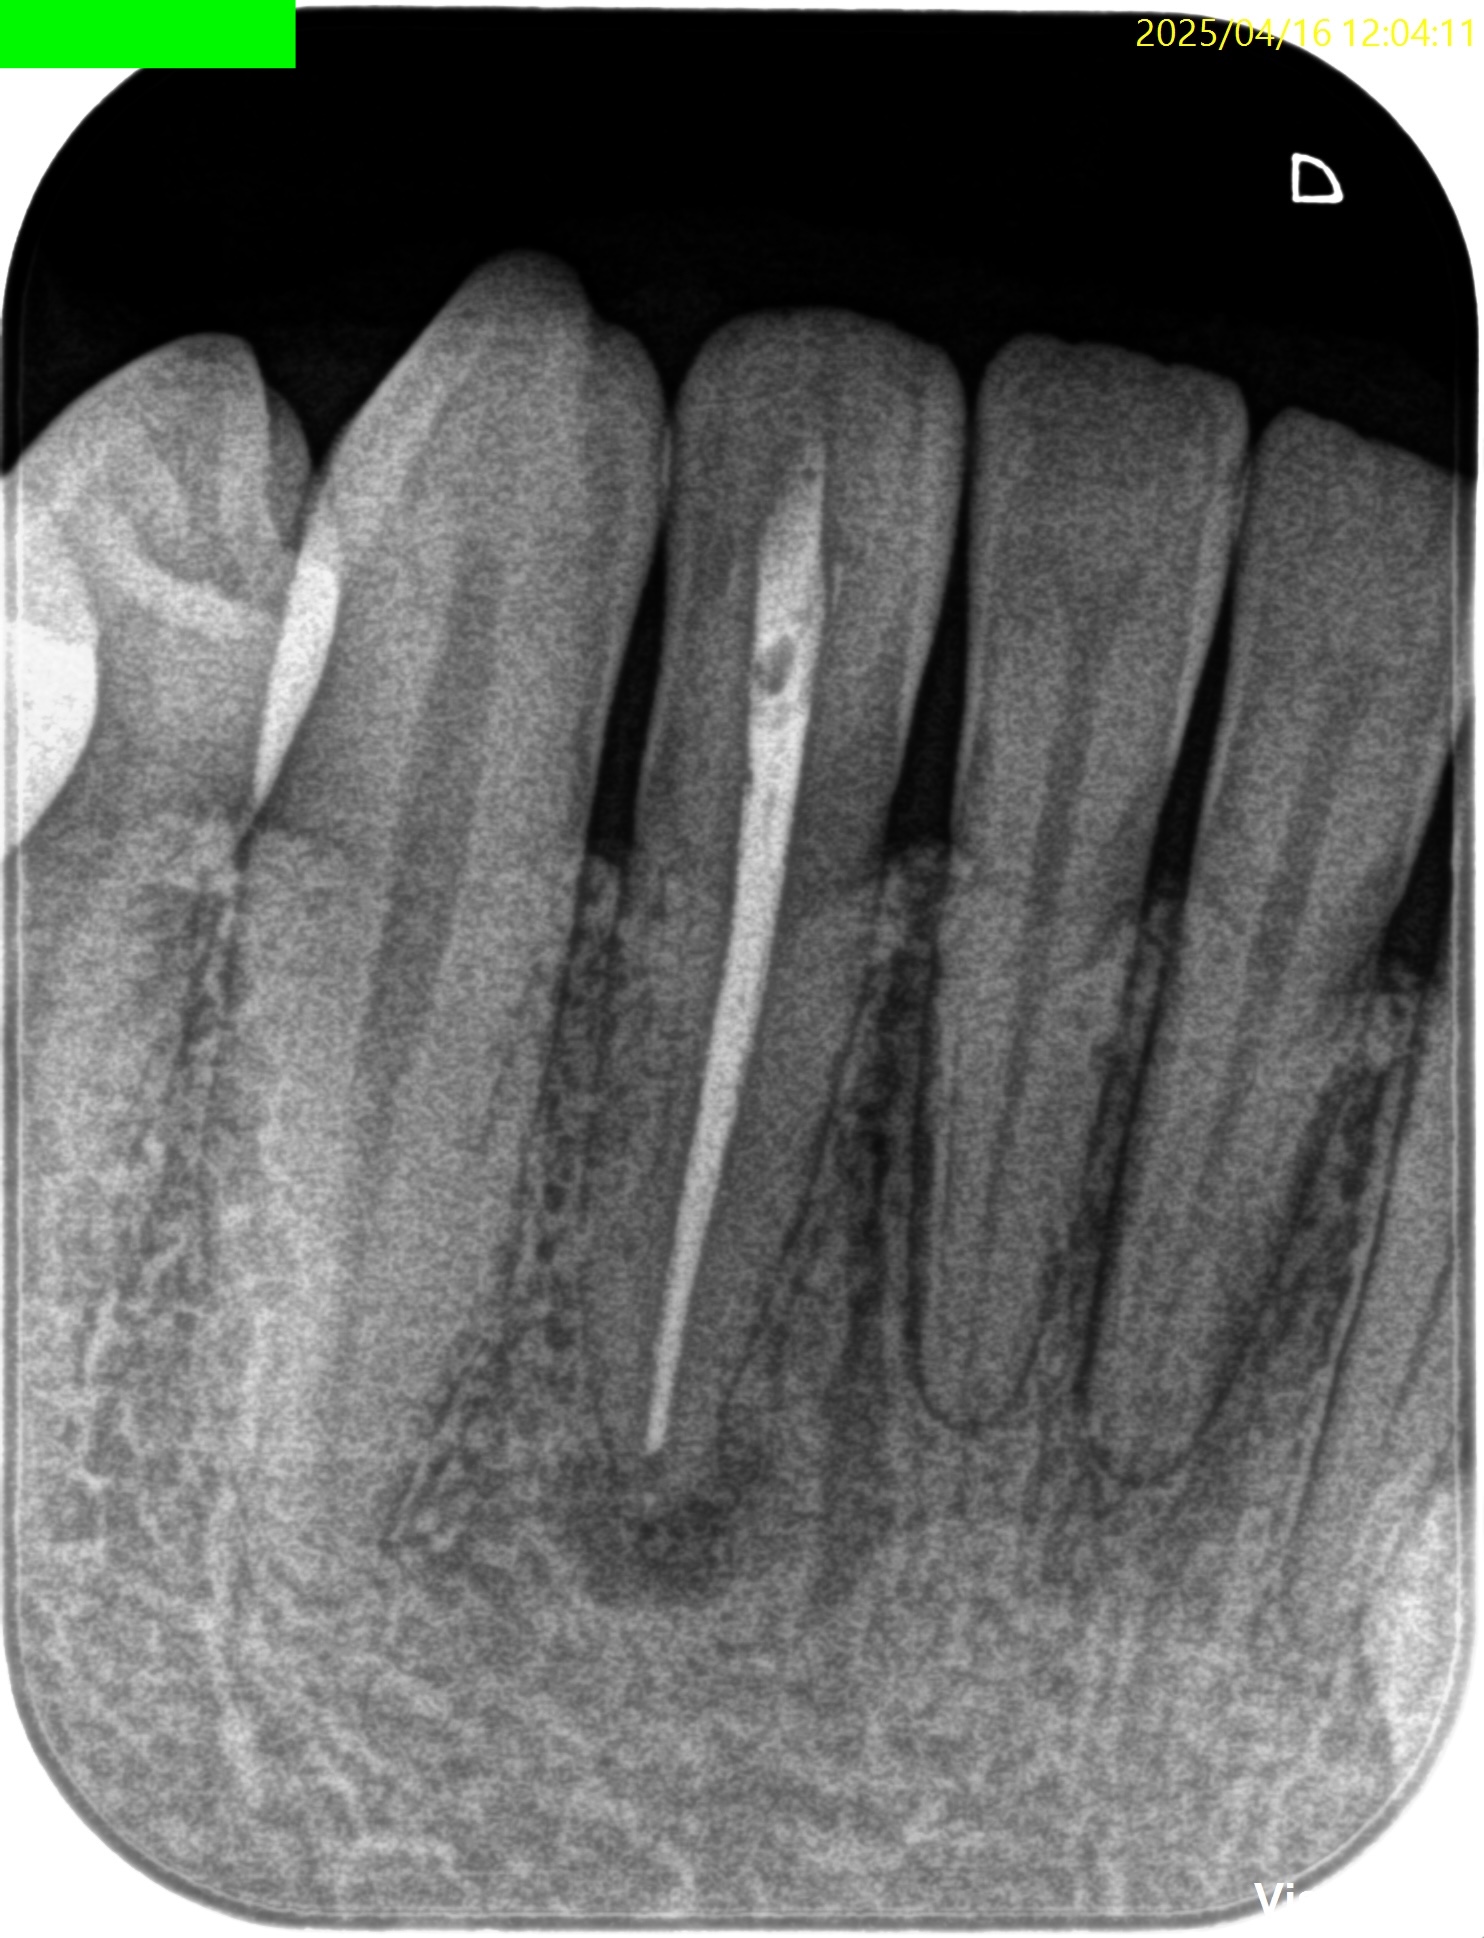

PA(2025.4.16)

形成し、所定サイズのGutta Percha Pointで根充した。